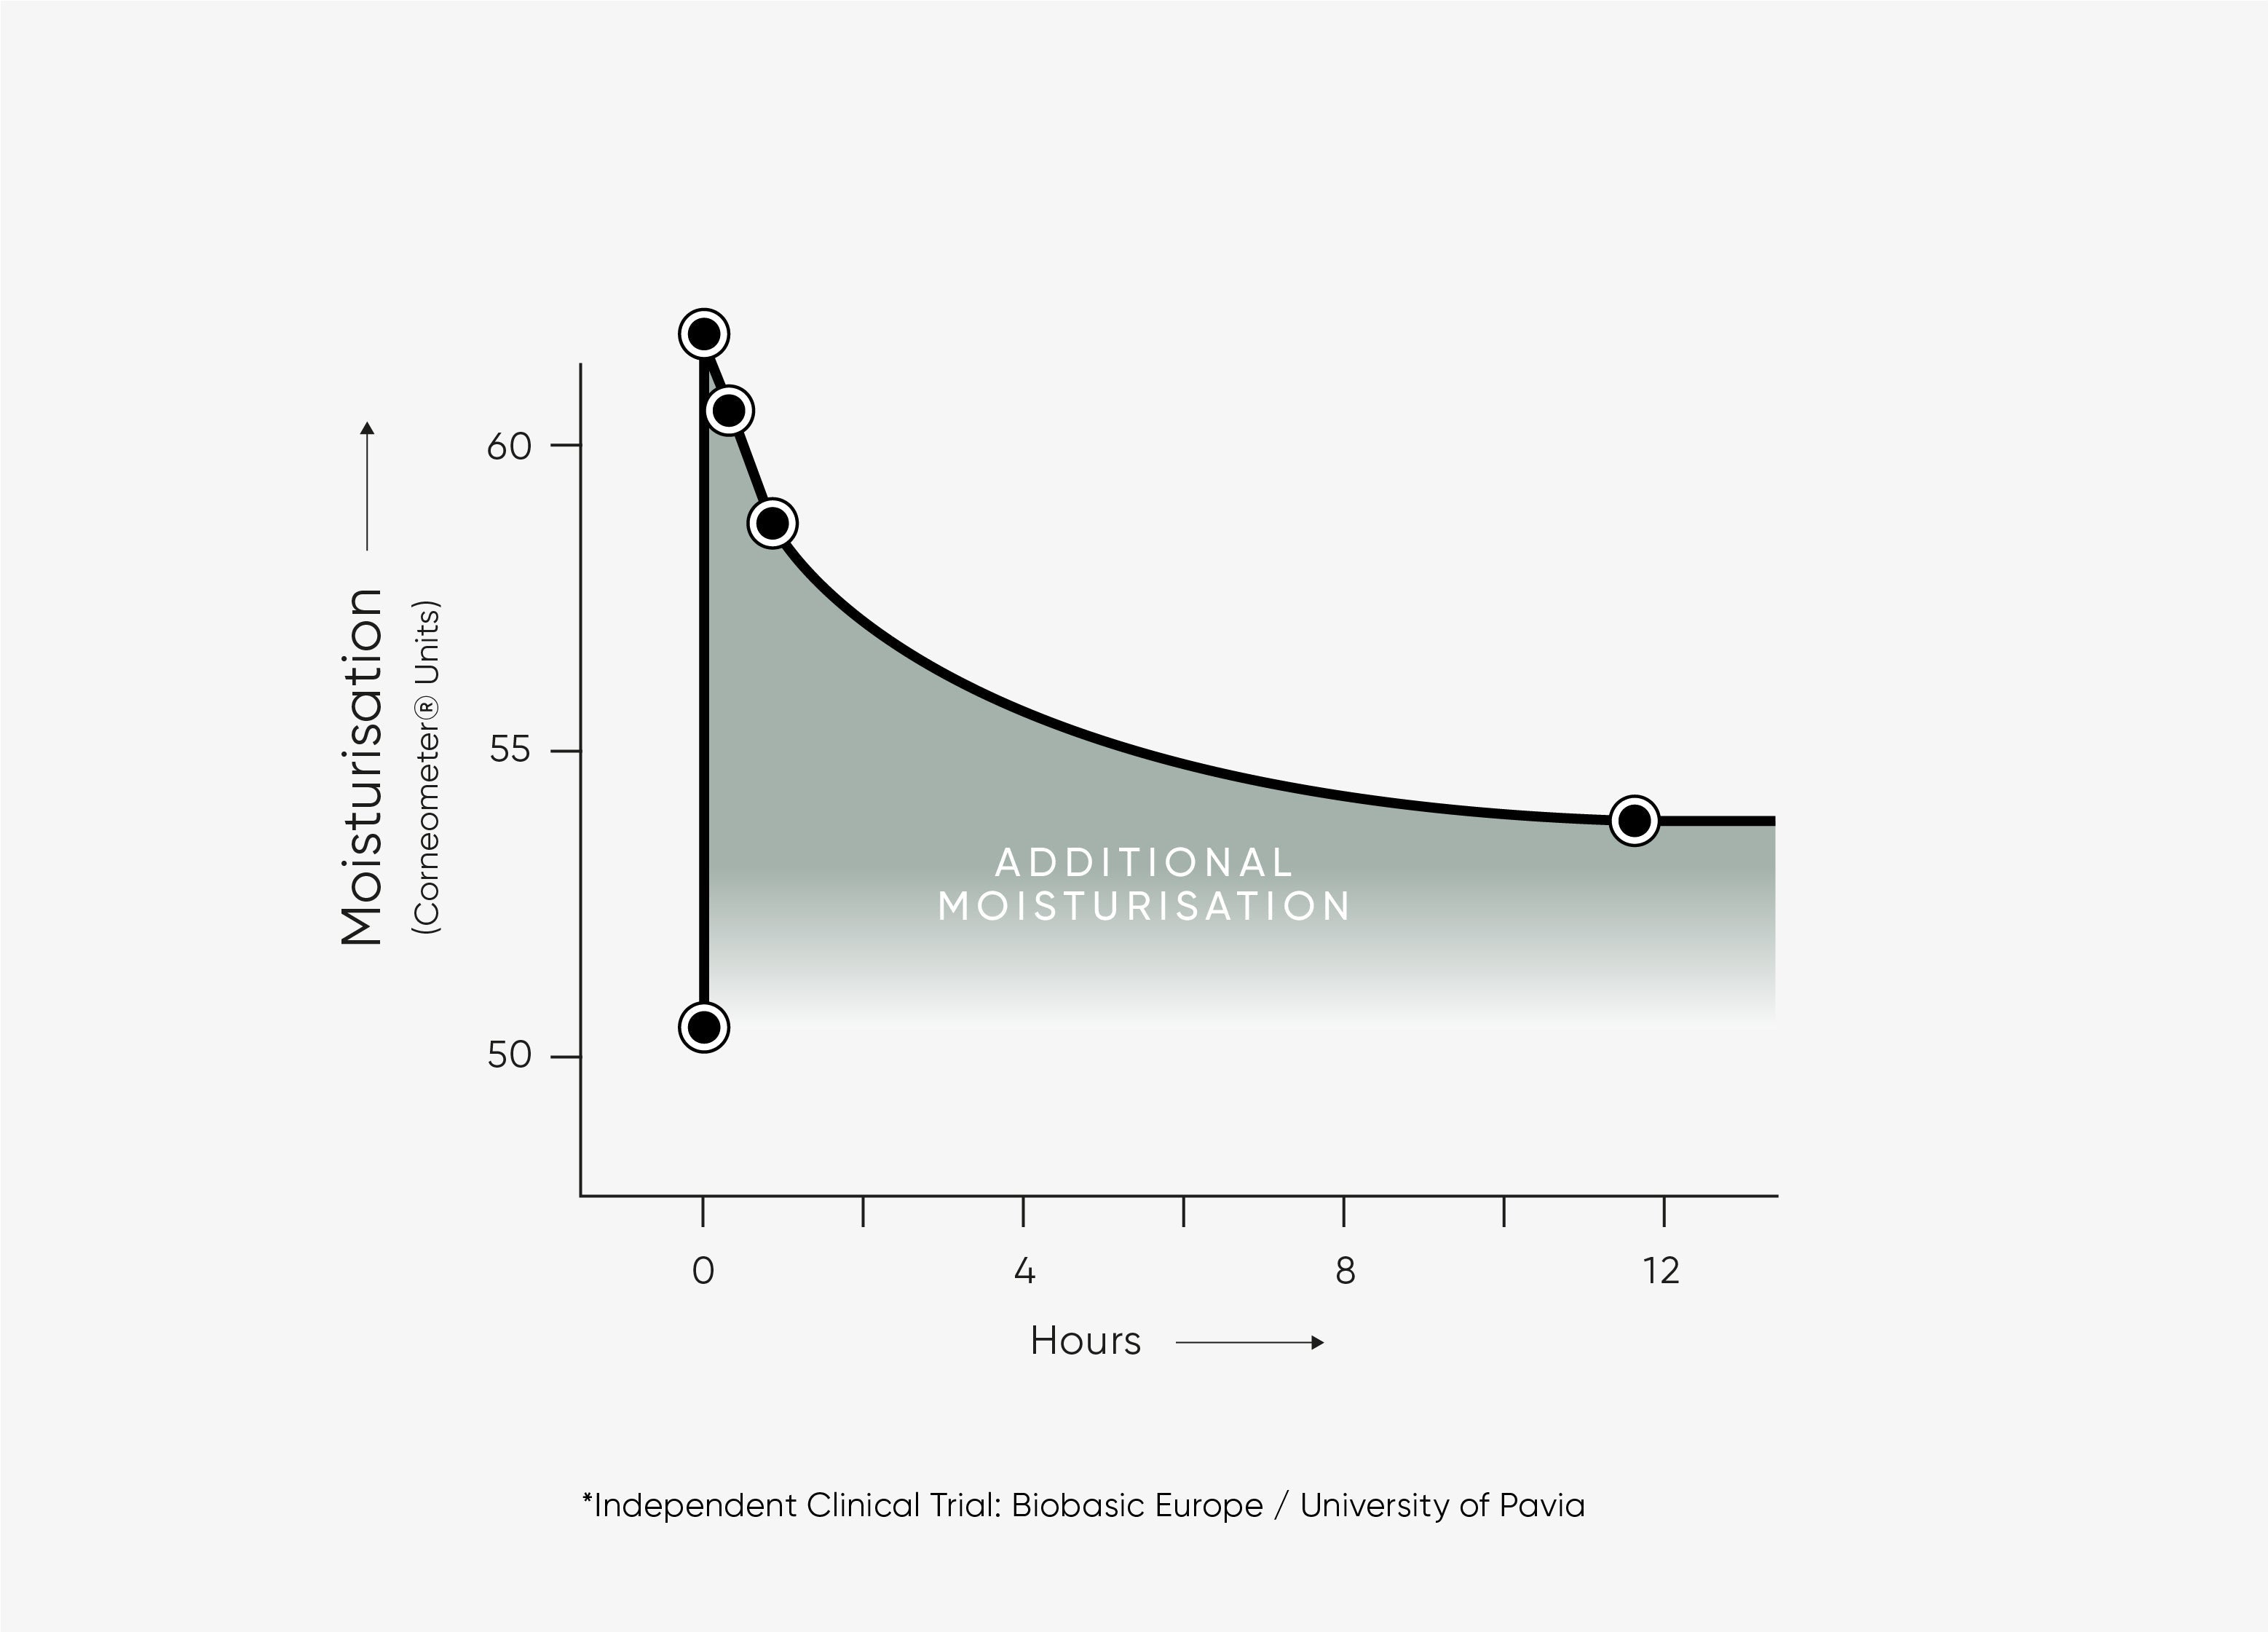

This lightweight, next-generation triple-weight Hyaluronic Acid serum is clinically proven to immediately plump the skin and provide hydration for up to 12 hours.

Clinically proven to hydrate skin over 12 hours, as well as immediately plump the skin.

This next generation Hyaluronic Acid serum is clinically proven to hydrate the skin over 12 hours. The unique triple weight blend is also proven to deliver an immediately plumping effect.

Clinically proven to hydrate the skin for over 12 hours with the triple-weight formula.